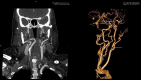

A 71-year-old lady presented with a symptomatic left cerebral occipital lobe infarct. With a history of paroxysmal atrial fibrillation a cardioembolic source was initially postulated. Prior significant bleeding while anticoagulated precluded warfarin therapy. Further investigations revealed a critical left internal carotid stenosis with a persistent fetal origin of the left posterior cerebral artery. She was successfully treated surgically and suffered no further ischaemic events. Physicians encountering posterior circulation stroke should be aware of this potentially treatable important diagnosis.